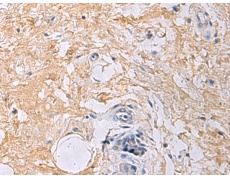

IHC positive control: |

Human gastric cancer |

IHC Recommend dilution: |

50-100 |